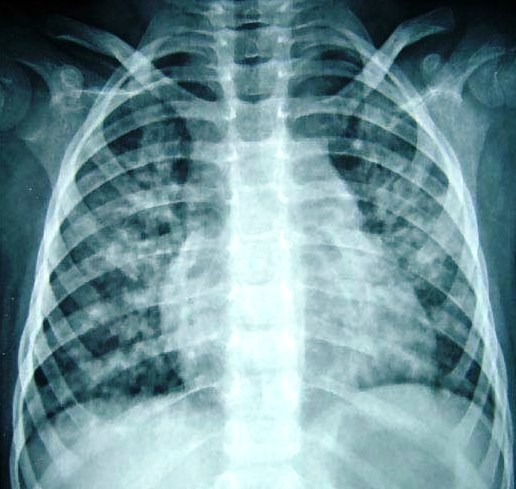

RN prematura, filho de mãe diabética, com quadro de desconforto respiratório nas primeias 24h de vida (taquipneia, tiragem, retração, BAN, cianose, gemência), Rx com infiltrado reticulogranular difuso/vidro moido, aerobroncograma e volume pulmonar reduzido…

Diagnóstico, fisiopatologia, e tratamento?

Síndrome do desconforto respiratório (Doença da membrana hialina)

Diminuição de surfactante no interior dos alvéolos… colapso alveolar na expiração